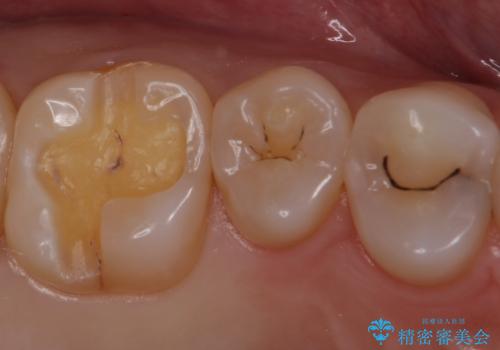

- 銀歯を白くしたいとのことで来院されました。

セラミックインレーでの治療をしていきます。